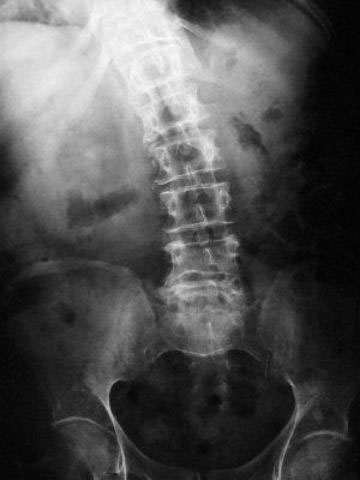

Osteoporosis. Cifosis.

Escoliosis. Espondilolistesis.

Artrosis lumbar

Artrosis lumbar con pinzamiento.